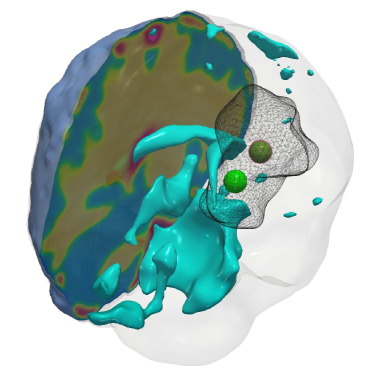

Fig. 4: (a) Description of the visualized brain sub-structures: The figure on the left shows an isometric view of the brain with different tumorous and healthy tissue sub-structures. The figure on the right zooms in on the tumor region and describes each structure. (b, c) Qualitative results for the artificial tumor test-case AT-C1 (a mono-focal, mostly proliferative tumor) with growth parameters ρ=8,κ=0.025formulae-sequencesuperscript𝜌8superscript𝜅0.025\rho^{\star}=8,~{}\kappa^{\star}=0.025. The images show the tumor data (gray wireframe), ground truth tumor initial condition (green volume), reconstructed tumor initial condition (magenta volume), ventricles (cyan volume), and a section of the patient brain geometry. We observe exact reconstruction for smaller tumors with sparsity constraints. The \mathboldL2\mathboldsubscript𝐿2\mathbold{L_{2}} solver fails to obtain the same reconstruction due to its inability to determine the correct reaction coefficient. We refer the reader to Tab. 4 for the quality of final tumor reconstruction.

Setup. We grow synthetic tumors in the segmentation of a statistical brain atlas [8] MRI scan (an atlas obtain by averaging several MR images). The segmentation labels are gray matter, white matter, and cerebrospinal fluid-filled ventricles (CSF). We use sparse initial conditions to grow the tumor to a significant size resembling clinical observations and invert for all biophysical parameters using the grown tumor at t=1𝑡1t=1 as input data to the solver. For all our test cases, we assume that the tumor grows and diffuses only in white matter. For this test-case, we observe the data everywhere, i.e., cd=0subscript𝑐𝑑0c_{d}=0. We consider the following variations:

(i) AT-C1: medium sized, mono-focal tumor ρ=8superscript𝜌8\rho^{\star}=8 κ=0.025superscript𝜅0.025\kappa^{\star}=0.025

(ii) AT-C2: large sized, mono-focal tumor ρ=12superscript𝜌12\rho^{\star}=12 κ=0.05superscript𝜅0.05\kappa^{\star}=0.05

(iii) AT-C3: multi-focal tumor, nearby seeds ρ=10superscript𝜌10\rho^{\star}=10 κ=0.025superscript𝜅0.025\kappa^{\star}=0.025

(iv) AT-C4: multi-focal tumor, distant seeds ρ=8superscript𝜌8\rho^{\star}=8 κ=0.025superscript𝜅0.025\kappa^{\star}=0.025

We report our quantitative results (performance measures, convergence, and solver timings) in Tab. 4 and visualize the reconstruction to qualitatively assess the performance of our solvers in Fig. 4 - Fig. 7. Each figure shows an isometric view of the patient brain with 3D volumes of the grown tumor data, ground truth, and reconstructed initial condition. We additionally visualize the ventricles and sections of healthy tissue to reveal the heterogeneity of the brain (and hence the tumor).

Observations. We observe that for the medium sized tumor (AT-C1) the reconstruction is nearly perfect for the CS solver while the \mathboldL2\mathboldsubscript𝐿2\mathbold{L_{2}} solver produces a lower performance, particularly in the inversion of the reaction coefficient. This is primarily due to the rich initial conditions produced by the \mathboldL2\mathboldsubscript𝐿2\mathbold{L_{2}} solver which impedes its ability to predict the correct reaction scaling using our method. We note that if the reaction scaling is known beforehand, the \mathboldL2\mathboldsubscript𝐿2\mathbold{L_{2}} solver can potentially have better performance (see [56, 16] for similar synthetic experiments). This problem is magnified for larger tumors (AT-C2 and AT-C3) where the predicted reaction coefficient shows about 66%percent6666\% and 54%percent5454\% relative error in the \mathboldL2\mathboldsubscript𝐿2\mathbold{L_{2}} solver for the two test-cases respectively (as compared to around 15%percent1515\% and 1%percent11\% error with sparsity constraints). The reconstruction in diffusivity also suffers similarly without enforcing sparsity. The final test-case shows a multi-focal tumor with two far apart proliferation sites. While both the solvers produce disjoint initial conditions for the tumor, the CS solver does better in reconstructing the model parameters: 2% versus 37% relative error in diffusivity and 9% versus 50% relative error in reaction coefficient. Both solvers show similar performance in their ability to fit the data (as measured by the relative error in final tumor reconstruction). Hence, our synthetic observations show consistent improvement in target parameter estimation for all test-cases with sparse initial conditions, without sacrificing the final tumor reconstruction quality.